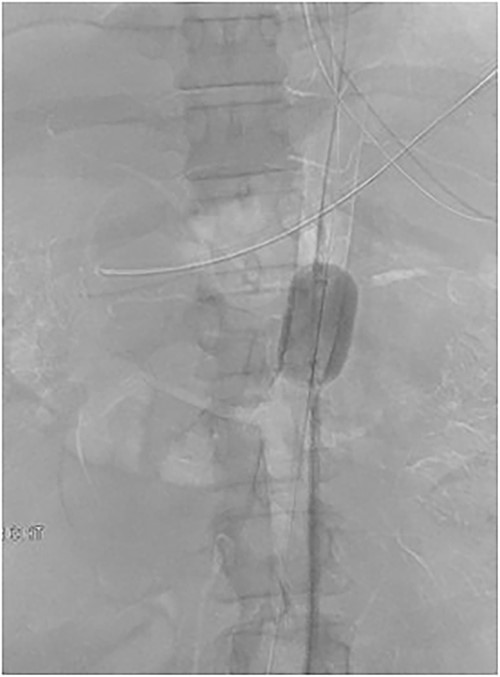

The patient was emergently transferred to the hybrid theatre with Trauma Surgery and Vascular Surgery teams in attendance. Ultrasound-guided right common femoral artery retrograde access was obtained and catheter angiography confirmed CA avulsion with good retrograde filling of branch vessels from the superior mesenteric artery (SMA). A 32 mm Coda® compliant balloon (Cook Medical, Bloomington IN) [4] was introduced and held in place with a 12Fr 45 cm long DrySeal sheath (WL Gore, Flagstaff AZ) and positioned at the juxta-coeliac aorta for rapid hemorrhage control whilst a midline laparotomy was performed. A transperitoneal approach was taken to reach the supra-coeliac aorta and the endovascular balloon was then inflated to occlude the thoracic aorta, CA and SMA (Fig. 4). The distal and proximal ends of the CA were formally ligated with 3/0 polypropylene, with the trifurcation remaining in continuity. Completion angiography demonstrated forward flow into the SMA with retrograde filling of the common hepatic and splenic artery via the gastroduodenal artery (GDA). Temporary abdominal closure was performed with nil further visceral injuries demonstrated on a subsequent relook laparotomy prior to closure. He was discharged 47 days following his injury.

Fluoroscopic image demonstrating endovascular balloon occlusion of aorta at the level of CA avulsion, superior to SMA and Bilateral Renal artery origins.